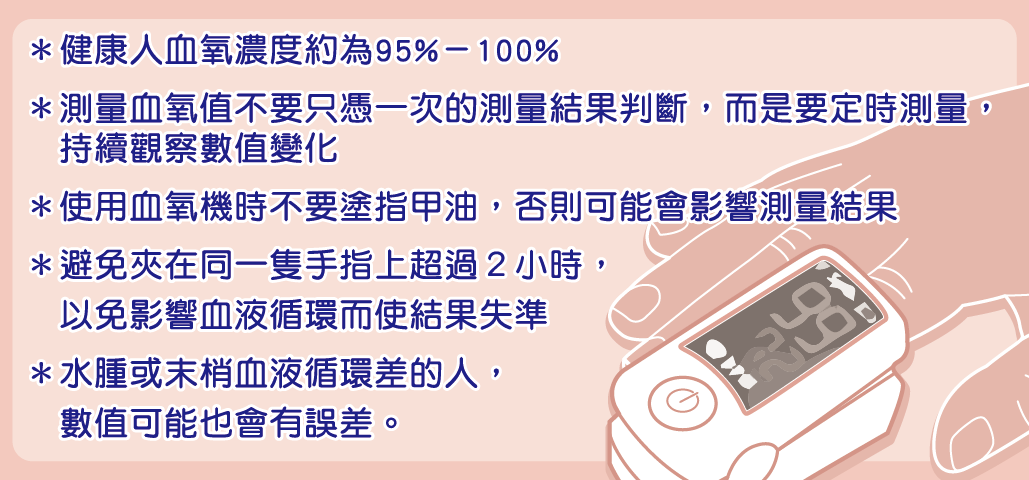

超夯血氧機,學會正確操作與判讀!

醫療用血氧機可用於測量及顯示動脈血氧飽和度(SpO2)及脈搏率(pulse rate)等資訊,是評估患者是否缺氧的利器,屬於第二等級醫療器材。其原理是以光學方式進行非侵入量測,利用含氧血紅素與去氧血紅素對不同波長的光吸收度差異,可計算出兩種血紅素光訊號的比例,進而推算出血氧飽和度。

什麼是血氧?血氧機該怎麼用?

新冠肺炎爆發後,不少民眾擔心COVID-19感染可能造成肺部發炎、降低血氧濃度,導致市售血氧機賣到缺貨!究竟什麼是血氧?使用時有哪些注意事項?食品藥物管理署(下稱食藥署)邀請家醫科黃農茵醫師為大家詳細說明。